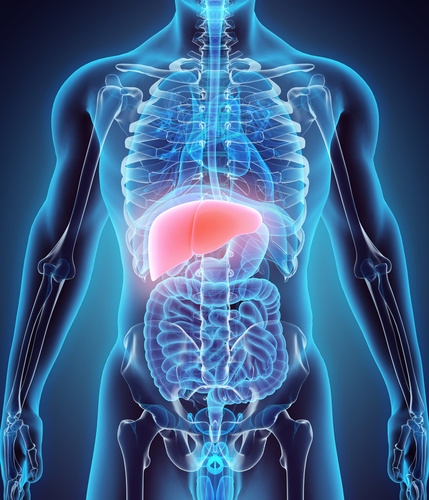

④肝臓を使う大腰筋リリース

手の感覚すら必要としない肝臓FCRメソッド

- 内蔵治療を習ったけど緩めるのに1分以上かかる、、、

- 正直、内臓の緩んでいる感覚がわからない、、、

- 内蔵治療に自信が持てない、、、

もしあなたがこんな悩みを持っているなら、この肝臓FCRメソッドを試してみて下さい。

内蔵治療を習ったけど、実際に患者さんに使ってみると出来ているのか自信が無いし、緩む感覚もイマイチ分からない。

しかし、このテクニックを使うことでそんな悩みとも無縁です。このテクニックをマスターする事で、たとえ内蔵治療が苦手なあなたでも、わずか10秒で患者の痛みを取り切る事が出来るようになるでしょう。

あなたの内蔵治療に革命を起こす、肝臓FCRメソッドを手に入れて下さい。

- 患者の信頼を一瞬で獲得する“肝臓FCRテクニック”(この治療を受けて感動しない患者はいません)